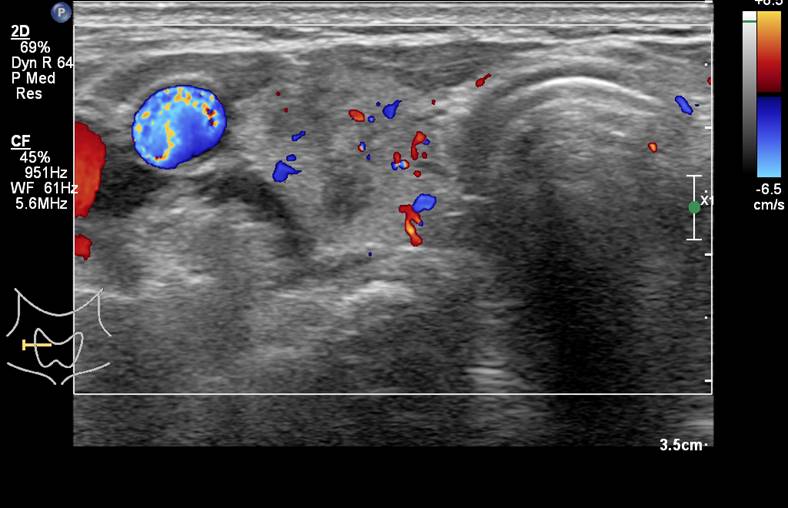

[360,] 64/F,Right anterior neck pain

다음 환자의 진단은?

Medullary thyroid carcinoma

Nodular hyperplasia

papillary thyroid carcinoma

follicular adenoma

Subacute thyroiditis